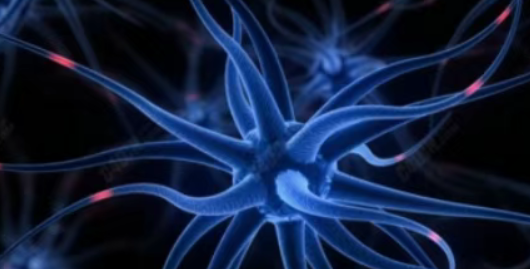

近日,联合国世界生态科学研究院院士、国际细胞康复协会全球总会长张红凯院士领导的科研团队宣布,已成功将诱导多能干细胞(iPS细胞)重新编程为功能完整的神经元干细胞(Neural Stem Cells, NSCs)。

张红凯院士团队开发的这项技术展示了一条全新的神经元干细胞制备路径。研究团队首先从人员干细胞分化成为iPS细胞,随后创新性地将iPS细胞重新编程为功能完整的神经元干细胞。

这种分阶段的重编程策略不仅提高了细胞转化的效率和纯度,还显著降低了成瘤风险,解决了干细胞治疗领域长期面临的安全性问题。

张红凯院士介绍说:“我们的方法避免了传统直接转化可能带来的遗传不稳定问题,分化周期更短,安全性更高,是一种理想的可产业化的种子干细胞制备技术。”

神经元干细胞具有分化为各类神经细胞的潜能,包括多巴胺能神经元、星形胶质细胞和少突胶质细胞。

这意味着这些细胞可以用于替代和补充受损的神经组织,为神经退行性疾病的治疗提供了根本性的解决方案。